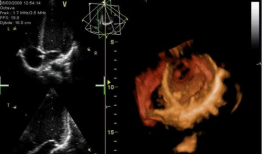

你知道吗?最近在网上流传着一个特别神奇的视频,它记录了心脏跳动的瞬间。这可不是普通的视频,它让我们仿佛能感受到心跳的力量,那种感...